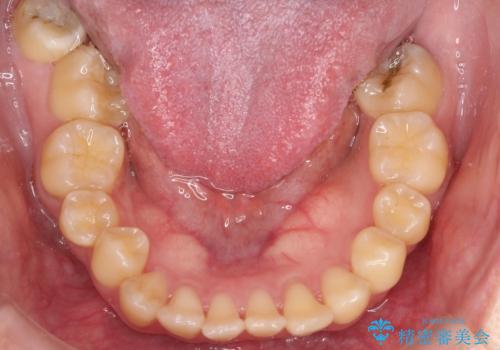

前歯の開咬とシザーズバイトを改善|インビザライン矯正

- 前歯が噛み合わない(開咬)ことと、奥歯の噛み合わせが交叉している(シザーズバイト)ことを改善するため、インビザラインによるマウスピース矯正を計画しました。精密な口腔内スキャナーを用いたシミュレーションで歯の移動経路を確認し、効果的な治療計画を立案。奥歯の咬合関係を整え、前歯の咬合を確立することを目指し、約1年半〜2年で治療を完了する予定としました。

前歯が噛まないため咀嚼が困難で、シザーズバイトにより噛み合わせに不調を感じていました。インビザラインを用いて、透明なマウスピースによる目立ちにくい矯正治療を実施。奥歯のシザーズバイトを改善した後、前歯の歯列を緻密に調整し、噛み合わせを整えました。定期的なマウスピース交換を通じて徐々に歯列が改善され、治療終了後には前歯が正常に咬合するようになり、噛み合わせの機能性と審美性が共に向上しました。